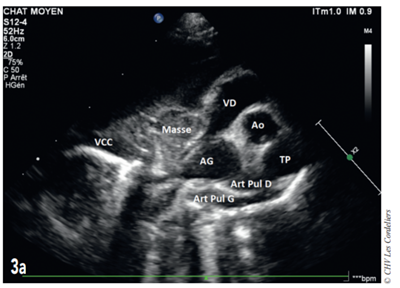

Un examen radiographique thoracique est réalisé (Fig. 1a et 1b) : il montre la présence d’une dilatation modérée des artères pulmonaires plus accentuée dans les lobes crânial droit et caudal gauche ; la silhouette cardiaque est élargie avec un vertebral heart size (VHS) = 9,8 (VU : 7,5 ± 0 3) 2 ; un épanchement pleural modéré associé à un arrondissement des bords pulmonaires responsable d’une opacité interstitielle modérée est mis en évidence. Il est observé une hépatomégalie modérée.

fig 1a et 1b

Fig. 1a – Radiographie thoracique de profil droit du 07/08/2017 : cardiomégalie (VHSM 9,8 ; VU : 7,5 ± 0,3 A.L. Lister), dilatation artérielle pulmonaire modérée, consolidation du lobe pulmonaire moyen droit et épanchement pleural modéré.

Fig. 1b – Radiographie thoracique de face du 07/08/2017 : cardiomégalie (silhouettecardiaque > 2/3 de la largeur thoracique), dilatation artérielle pulmonairemodérée,consolidation du lobe pulmonaire moyen droit et épanchement pleural modéré.